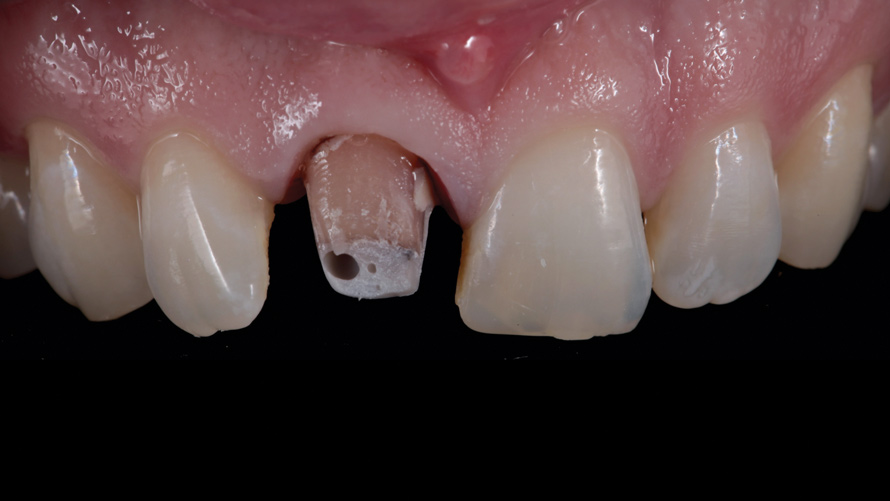

(5.) Case 1: Discolored stump and resin core immediately following sectioning and removal of the existing ceramic restoration.

Figure 5

The prosthetic and endodontic protocols were nearly identical for all phases of treatment in both cases. At the first operative visit, the existing ceramic crown was carefully sectioned and removed (Figure 5 and Figure 6). This was followed by the removal of any existing supragingival core materials in the first case. Next, the highly chromatic underlying natural stump shade was recorded, and a provisional restoration was fabricated and luted with temporary cement. Each patient was then immediately dismissed to the endodontist for same-day elective root canal therapy and internal bleaching treatment with the walking bleach technique.